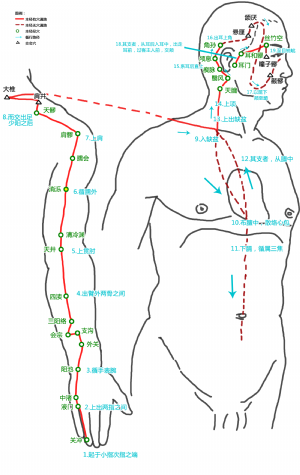

消濼爲經穴名[1](xiāoluò[2]TE12) 。出《鍼灸甲乙經》。屬手少陽三焦經[2]。消即消除,濼爲泊名,此穴如清涼之水,能清熱消渴,故名消濼[2]。消濼穴主要用於頭項疾患等:如寒熱,頭痛,齒痛,頭暈,頸項強急,肩背拘急,肩周炎,項強,臂痛,上肢麻痹,肩背痛,癲癇,偏頭痛,頸項痛,背部腫痛,頸椎病,頸項強痛,背腫等。

標準定位:消濼穴在臂外側,當清冷淵與臑會連線的中點處[4]。

消濼穴位於臂後區,肘尖(EX-UEl)與肩峯角連線上,肘尖上5寸[4]。

消濼穴位於肘尖(尺骨鷹嘴)與肩髎穴連線上,當清靈淵與臑會穴連線之中點處,前臂盡力旋前,在肱三頭肌外側頭隆起的下緣[5]。

消濼穴在上臂的位置

消濼穴在上臂的位置

正坐垂肩,前臂旋前,先取三角肌後下緣與肱骨交點處的臑會穴,當臑會與清冷淵之間的中點處是該穴。

消濼穴位於臂後區,肘尖(EX-UEl)與肩峯角連線上,肘尖上5寸[5]。